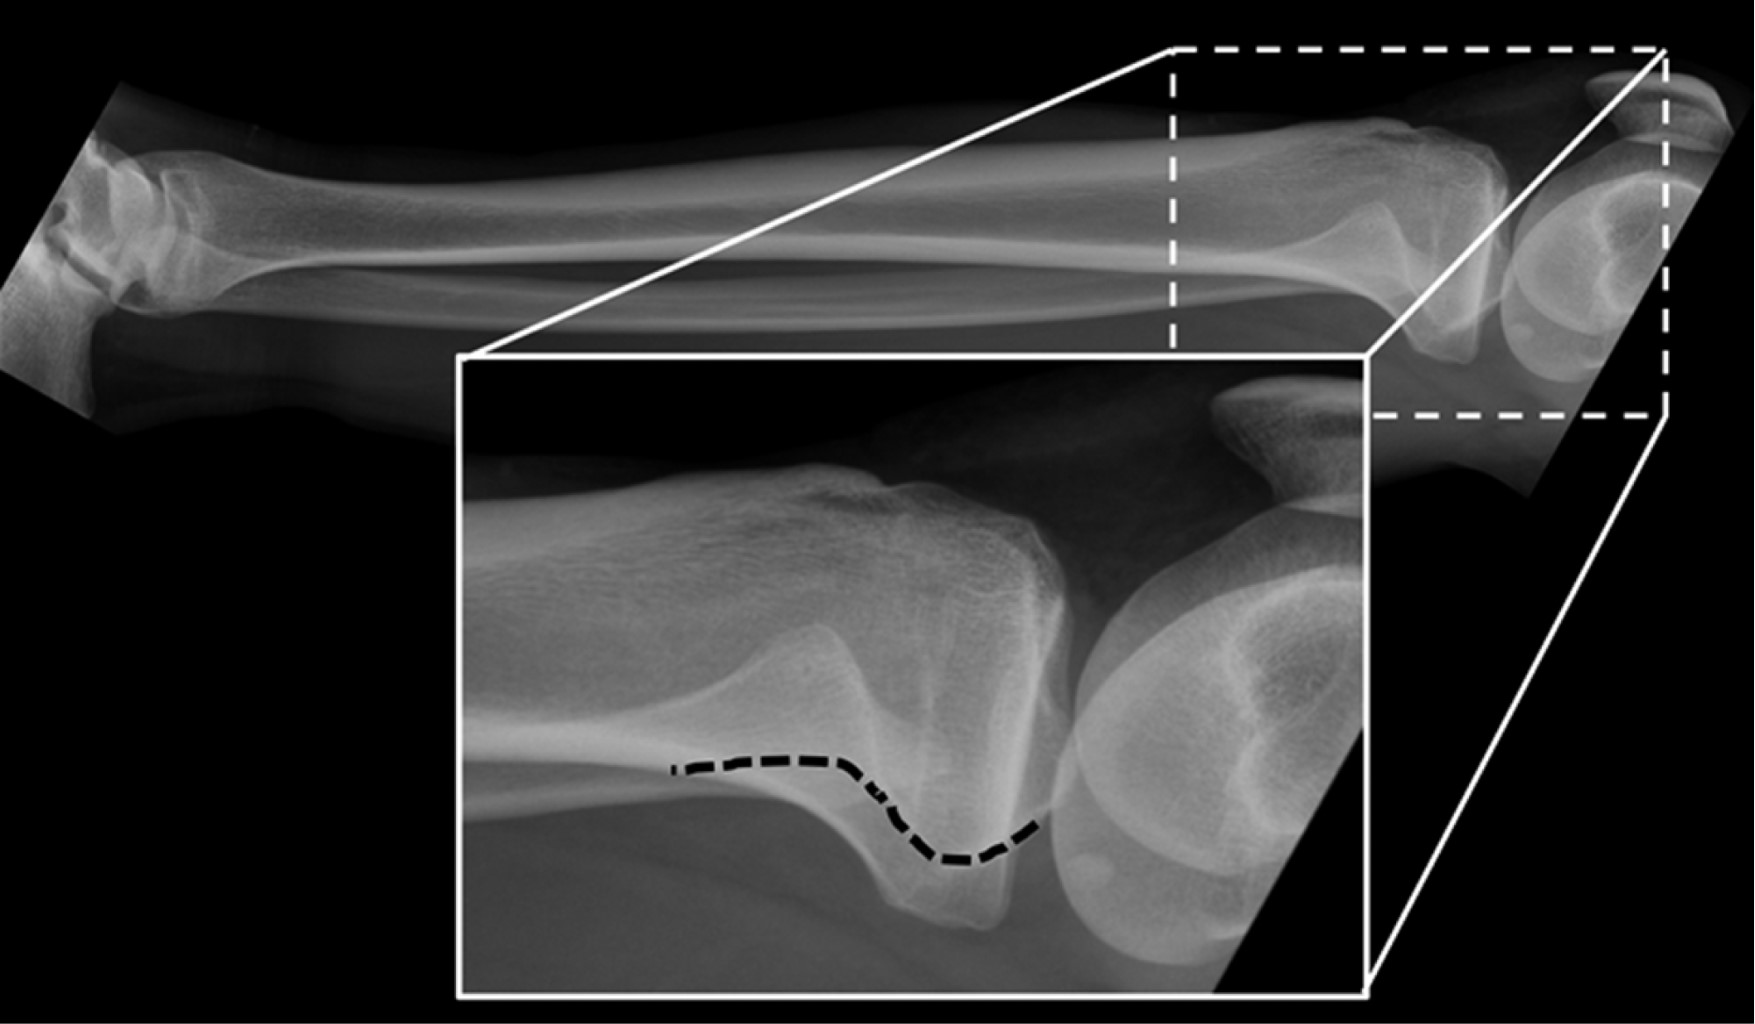

Para descartar una lesión ósea aguda, se solicitan radiografías de rodilla derecha anteroposterior (AP), lateral, axial de patela y de pierna derecha AP y lateral (Figura 1). Las imágenes descartan fracturas óseas y son informadas sin signos de LTFP ni otras alteraciones.

Evaluación imagenológica: frente a un trauma de rodilla, el estudio debe iniciarse con radiografías AP, lateral y axial de patela de la rodilla afectada. En la proyección AP, el aumento del espacio interóseo proximal, visto a través de la ausencia de superposición de la cabeza fibular sobre el margen lateral del cóndilo externo de la tibia sugiere una luxación lateral.15 Sin embargo, la única referencia objetiva descrita en la literatura es la de Resnick y colaboradores que permite identificar una luxación tibiofibular proximal en una proyección lateral.16 Se debe trazar la línea de la cresta posteromedial del platillo lateral de la tibia y evaluar su relación con la cabeza fibular (Figura 3). Se considera fisiológico si esta línea se proyecta sobre la porción media de la cabeza fibular; si la mayor parte de la cabeza se encuentra anterior a la línea de Resnick, traduce una luxación anterior; lo contrario sucede en las luxaciones posteriores.16 A pesar de su constante descripción,2,11,16,17,18,19 no hay estudios que demuestren su sensibilidad y especificidad.

En resumen, no existe en la actualidad un consenso respecto al orden y al adecuado uso de imágenes al momento de sospechar este tipo de lesiones. Los autores consideran suficiente iniciar, como primera línea, con radiografía AP y lateral comparativas. En el caso de persistir con alta sospecha clínica con radiografías no concluyentes, solicitar una tomografía computarizada (TC) o resonancia magnética (RM) considerando las ventajas y desventajas de cada modalidad. Analizando el caso clínico ilustrado, se evidencia una variante anatómica oblicua en la proyección lateral, la cual apoya el diagnóstico (Figura 1). Por otro lado, complementar con radiografías AP y lateral comparativa y una TC en el ambiente de urgencia hubiese asistido en el diagnóstico. Sin embargo, el paciente se presentó en el servicio de urgencias durante la pandemia de COVID-19, por lo que rechazó la evaluación en agudo con una TC.